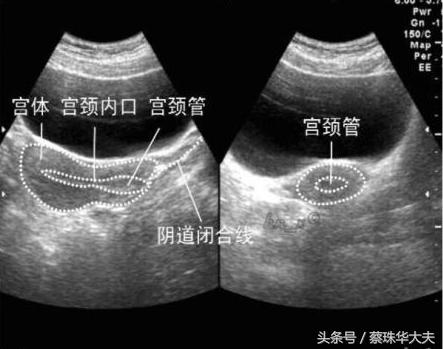

如果小胚胎长错了位置,长到输卵管内,那小神探也不怕,神探位置稍微变动一下,转到侧穹窿,一会儿就找到卵巢和旁边的输卵管。

而腹部探头(神探妈妈)虽然有时候比小神探厉害,但神探妈妈眼睛看表面东西厉害,找深部东西没有小神探那么灵活。

神探妈 妈看子宫和卵巢输卵管只有通过肚皮皮肤,肚皮下脂肪,才能照到达子宫表面,而且有时候爱捣乱的肠子还会来砸场。